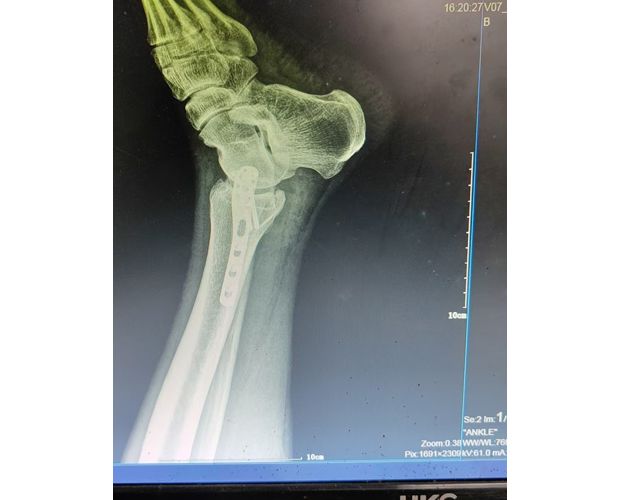

2月4日,何店镇中心卫生院接诊一名左踝关节外伤患者,经影像检查,确诊为左胫、腓骨下段骨折。外科医生姜稳迅速完成术前检查及病情评估,并与患者及家属深入沟通治疗方案。在患者强烈要求于本院进行手术的情况下,为最大限度保障手术质量与安全,该院特邀请医共体牵头单位——曾都区人民医院脊柱创伤外科专家团队前来指导。

本次帮扶由曾都区人民医院脊柱创伤神经外科主任徐三军带队,专家团队抵达后立即完成手术风险评估及术前准备。手术过程中,徐三军主任严格规范完成各项手术操作,并同步结合手术步骤,为该院外科医师详细讲解骨折手术的关键要点、操作技巧、术中注意事项及术后康复要领。通过“手把手”的实战带教,专家将丰富的手术经验与规范的诊疗思路倾囊相授,让该院医护人员在实操中学习,在过程中成长。